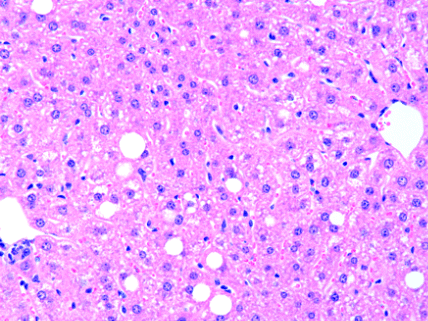

Nesta práctica imos extraer DNA dun tecido, no noso caso fígado. Este tecido é moi axeitado xa que conten relativamente pouca substancia intercelular e os hepatocitos teñen un núcleo bastante grande en relación co citoplasma.